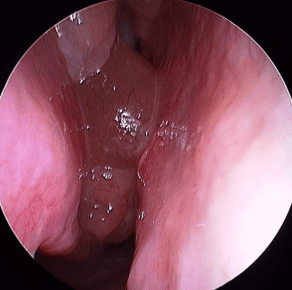

- Nasal endoscopy to detect polyps or inflammation

3. Nasal Polyps

Soft growths inside the nasal cavity interfere with airflow and smell perception.